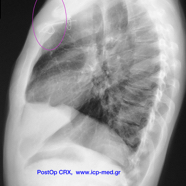

ΕΙΚΟΝΕΣ 12–14: Μτχ/κό αποτέλεσμα.